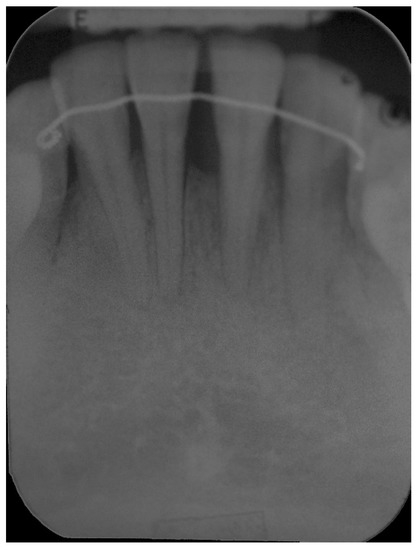

5. Materials and Methods

6. Results